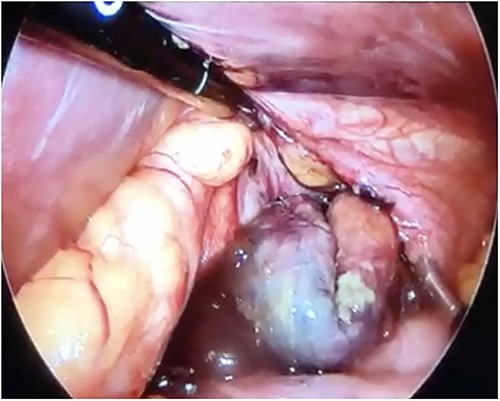

Initial treatment included intravenous crystalloid fluid repositioning, pain management, and antibiotic therapy. After diagnosing perforated gastric volvulus on a computed tomography (CT) scan, a diagnostic laparoscopy was performed. A hiatal hernia was identified with protrusion and twisting of the gastric body (Fig. 2). As the stomach body was reduced back to the abdominal cavity, a 1.5-cm perforation at the level of the greater curvature was detected. It was primarily sutured and covered with an omental patch (Fig. 3). The ischemic hernia sac containing the stomach was filled with food scraps and resected (Fig. 4). Laparotomy conversion was necessary due to hemodynamic instability attributable to the laparoscopic pneumoperitoneum. A 180° anterior fundoplication of the stomach (Dor’s Technic) associated with diaphragmatic raffia was performed. Gastric air leak testing was negative and intraoperative endoscopy showed no other defects on the gastric wall.

Laparoscopic view demonstrating an approximately 1.5-cm lesion at the level of the greater curvature of the stomach.